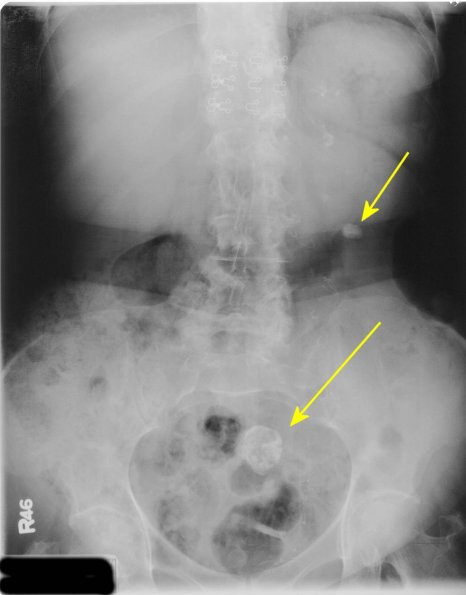

What is going on in this KUB? This patient also has a left renal stone, but ignore that and focus on the other thing.

This is actually a calcified leiomyoma

Uterine fibroids can sometimes calcify on the outside and look similar to stones.

Teratomas in this area might also grow teeth, which appear as masses of calcium.